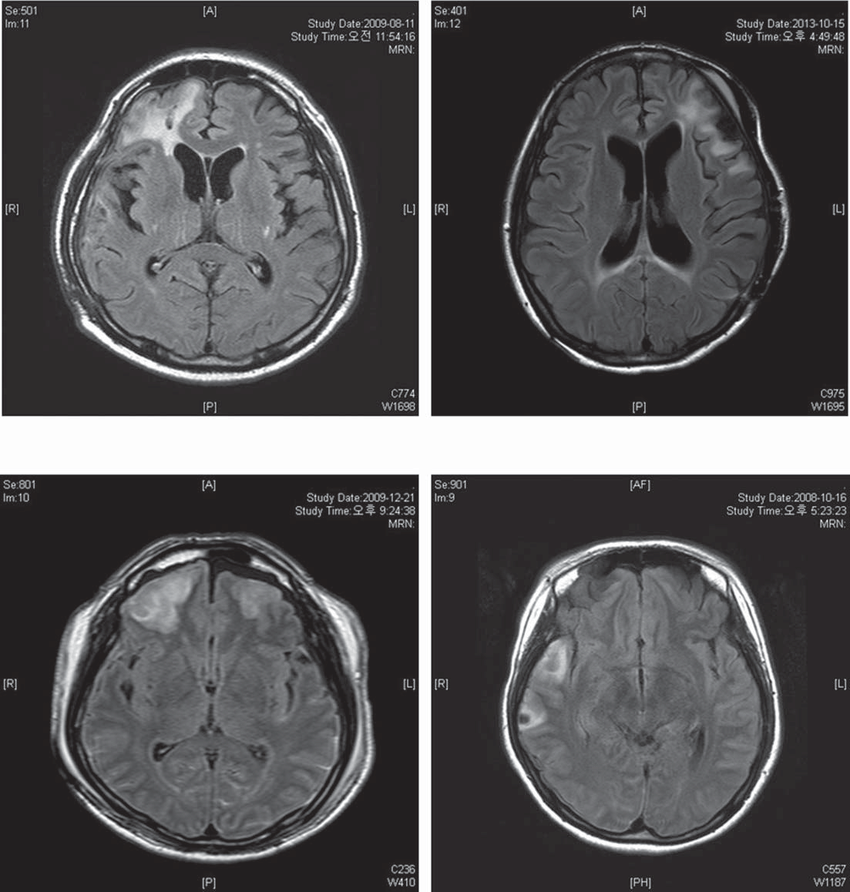

画像引用元:ReserchGate

画像の説明

- 左上の画像(2009年8月11日)

- 観察ポイント: 脳の全体的な構造が比較的正常に見えますが、外傷の兆候として小さな異常が見られる可能性があります。

- 特徴: 脳室の拡大や明らかな損傷は見られません。

- 右上の画像(2013年10月15日)

- 観察ポイント: 脳室の明らかな拡大が見られ、脳の萎縮が進行している可能性があります。

- 特徴: 脳室の拡大は、脳組織の減少を示しており、これは慢性的な損傷や萎縮の結果である可能性があります。

- 左下の画像(2009年12月21日)

- 観察ポイント: 初期の損傷が確認され、脳の特定の領域に異常が見られる可能性があります。

- 特徴: 小さな出血や浮腫の兆候が示されている場合があります。

- 右下の画像(2008年10月16日)

- 観察ポイント: 最初の損傷後の画像であり、初期の脳損傷の状態が見られます。

- 特徴: 脳組織の損傷や出血、浮腫の初期兆候が見られることがあります。

解説と考察

これらの画像は、時間の経過に伴う頭部外傷後の脳の変化を示しています。初期の画像では、明らかな損傷が見られない場合でも、時間の経過とともに脳の萎縮や脳室の拡大が進行していることが確認できます。これは、慢性的な脳の損傷や神経細胞の減少を示しており、TBI(外傷性脳損傷)の典型的な経過を反映しています。

具体的なポイント

- 脳室の拡大: 脳組織の減少によるもので、慢性的な損傷の結果として見られます。

- 脳の萎縮: 長期間にわたる神経細胞の損失と関連しています。

- 出血や浮腫: 初期の損傷後に見られる可能性があり、急性期のTBIの特徴です。